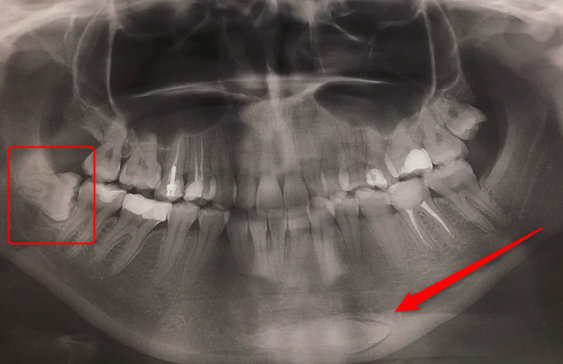

Ещё в школе на левую нижнюю шестерку была установлена пломба (амальгама). По прошествии десяти лет она выпала и вместе с ней отломился большой кусок зуба. Под пломбой был глубокий кариес. Врач установила новую пломбу, без удаления нерва. Болевые ощущения периодически возникали и после лечения, но через три года боль начала усиливаться. И я обратилась к другому врачу с этой проблемой. Врач обнаружила воспаление на корне зуба. Мне удалили нерв, заложили лекарство. В три посещения после лечения воспаления мне установили постоянную пломбу. На три месяца боль пропала, но после появилась вновь. Я обратилась к врачу снова. Мне сделали снова снимок, на котором врач не обнаружила проблему, воспаления не было. Сделали КТ трёх зубов (36,37,38). После снимков врач предположила, что проблема может быть из-за 38 зуба, который находится в десне и расположен перпендикулярно росту всех зубов. И практически упирается в корни 37 зуба. Но болит не 37, а 36 зуб.

Конечно лучше было бы прислать снимок, но раз доктора говорят, что воспалений на корнях 36 и 37 зубов нет, то, скорее всего дело в 38 зубе. От него может болеть не только, какой-то конкретный зуб, но и вся челюсть. Просто он давит именно на тот нерв, который идёт к 36 зубу. Удалите 38 зуб, и после заживления лунки уже можно будет точно сказать из-за него были боли или нет. В любом случае начните решать проблему с удаления.

На снимке, в области подбородка какое-то образование, отмечено стрелочкой, это зуб? Если да то, как он там оказался и нужно ли с ним что-то делать?

• Это ваш зуб мудрости, к сожалению, он так вырос. Данный зуб необходимо удалить как можно раньше. В противном случае его передвижение может нарушить целостность зубного ряда. Обратитесь к грамотному челюстно-лицевому хирургу.